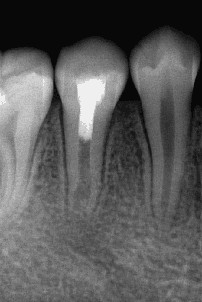

通过牙髓再生治疗,促进牙髓坏死的年轻恒牙牙根进一步发育,牙髓活力测试呈阳性 。

术后3